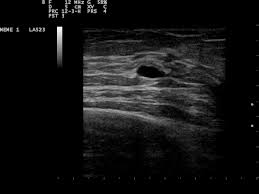

Any area that does not look like normal tissue is a possible cause for concern. Magnetic resonance imaging (mri) of the breast — or breast mri — is a test used to detect breast cancer and other abnormalities in the breast. Breast cancer and some noncancerous (benign) breast conditions can appear white on a mammogram. Microcalcifications, which look like white specks on a mammogram. What does an abnormal mammogram look like? Breast mri images are combined, using a computer, to create detailed pictures. Mammograms may show suspicious areas of the breast, white spots, and microcalcifications. In addition to mammograms, ultrasound and mri may also be used to take a closer look at changes in the breast. Tumors are likely to be smaller when doctors detect them early, which can. This type of cancer also changes the appearance of your breasts. A lump or tumor will show up as a focused white area on a mammogram. This appears most commonly as streaking, known as linear enhancement. There are few risks associated with mammography.

Breast Cancer Ge News from www.ge.com Healthy mammograms can still vary in appearance. The dye collection in the breast can also look clumpy or appear in a section of the breast, depending on the involvement of dcis. It can also be used to investigate the cause of breast problems, such as a breast mass, pain and nipple. Cancers may be seen as masses (like a ball, but usually with an irregular shape), areas of asymmetry that resemble normal tissue, calcifications (white specks), and/or areas of architectural distortion (imagine the puckering caused by pulling a thread in a piece of fabric). There are few risks associated with mammography. If you've had a mammogram before, the radiologist should compare your old mammogram to the new one to look for changes. After a mammogram that didn't show anything, and a sonogram that found the lump, i was diagnosed with stage 2 breast cancer. The doctor reading your mammogram will be looking for different types of breast changes, such as small white spots called calcifications, larger abnormal areas called masses, and other suspicious areas that could be signs of cancer.